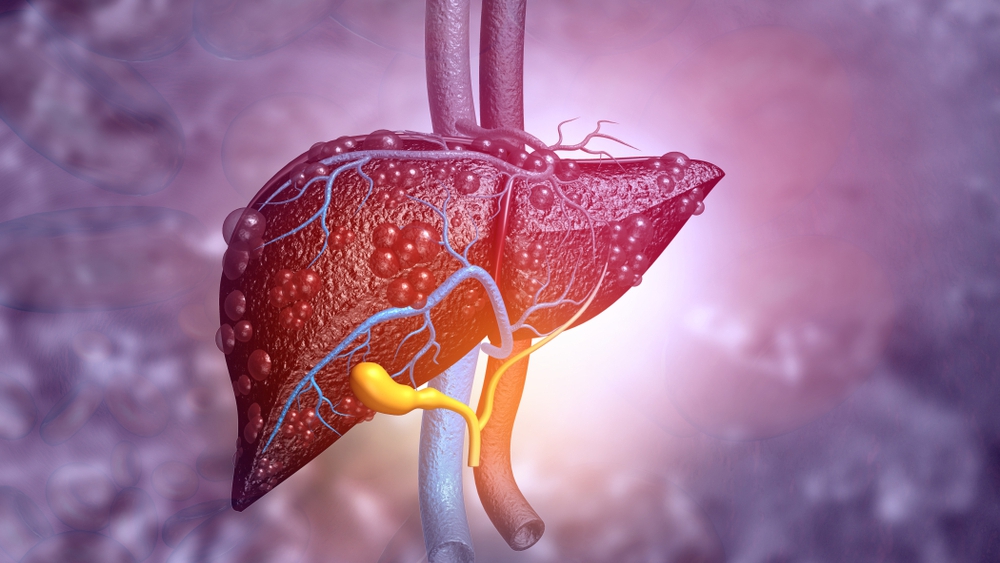

Liver disease remains a major health concern, causing an estimated 2 million deaths worldwide per year. While healthy livers have a nearly unlimited ability to regenerate themselves, that is not the case for livers that are damaged. As a result, surgeons treating a patient with primary liver tumors are limited in how large of a section of the liver can safely be removed to avoid liver failure.

The study found that a drug called HRX215 inhibits the MKK4 protein found in liver cells. That appears to trigger the self-healing function of the liver, allowing it to regenerate. Before the drug was tested in 48 healthy volunteers within the phase 1 study, it was investigated in animal models. The preclinical study was able to show that the use of HRX-215 increased liver regeneration and prevented liver failure, even after the removal of 85% of the organ. The phase 1 study found excellent safety and tolerability of the drug in people. Additional clinical trials are needed to establish the efficacy of the drug in humans.

Researchers are hopeful that this discovery will one day create more surgical options for patients with advanced liver tumors by allowing more of the liver to be safely removed. It also has the potential to benefit patients with acute and chronic liver failure. This drug could potentially allow for successful liver transplants from a smaller portion of a healthy donor’s liver, and thus posing less risk to healthy donors. Often, this liver is too small to successfully take over the function of the full-sized liver removed from the recipient. The hope would be that this drug could allow for rapid liver regeneration, creating a new safe transplant option for people struggling with liver failure. This drug also could potentially eliminate the need for a liver transplant for some patients.